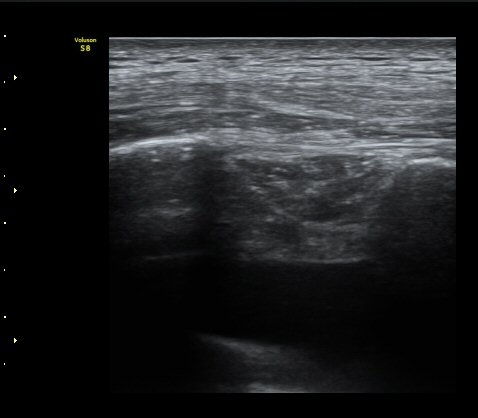

°¥ºñ»À ÇÇÁú°ñ ¿¬°á¼º ¼Ò½Ç°ú ¾à°£ÀÇ ÀüÀ§, ¿¬ºÎÁ¶Á÷ ºÎÁ¾ÀÌ °üÂûµÊ (loss of cortical continuity and soft tissue swelling of rib)  »çÁø 2

°¥ºñ»À °ñÀý ÈÄ Å« ÀüÀ§°¡ °üÂûµÊ(fracture with displacement) »çÁø 3